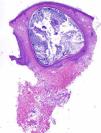

We present the case of a 48-year-old man with history of adenocarcinoma of the lung with cerebral metastases for which he received palliative treatment with holocranial radiotherapy at a dose of 30Gy in 10 fractions. The radiation fields included the auricles of the ear (2 opposing lateral photon beams to the central nervous system); the total dose received by the auricles of the ear was calculated as between 20 and 25Gy. The patient came to our outpatient clinic for asymptomatic lesions that had arisen on the posterior aspect of the auricles of both ears 3 months earlier. Since his youth he had occasionally presented isolated lesions of a similar appearance, but the multiple lesions had developed a month after the radiotherapy. On examination, multiple millimetric whitish papules with a shiny surface on an erythematous base were found in groups bilaterally on the auricles of the ears (Figs. 1 and 2). Punch biopsy revealed an infundibular follicular cyst full of orthokeratotic keratin (Fig. 3). Postradiotherapy milia en plaque was diagnosed based on the patient's past medical history and the clinical and histologic findings.

Histology reveals small cysts containing orthokeratotic keratin, located in the dermis. The cysts are lined by a squamous epithelium with a granular layer, and are accompanied by a mild mixed or lymphocytic perivascular infiltrate.2,4